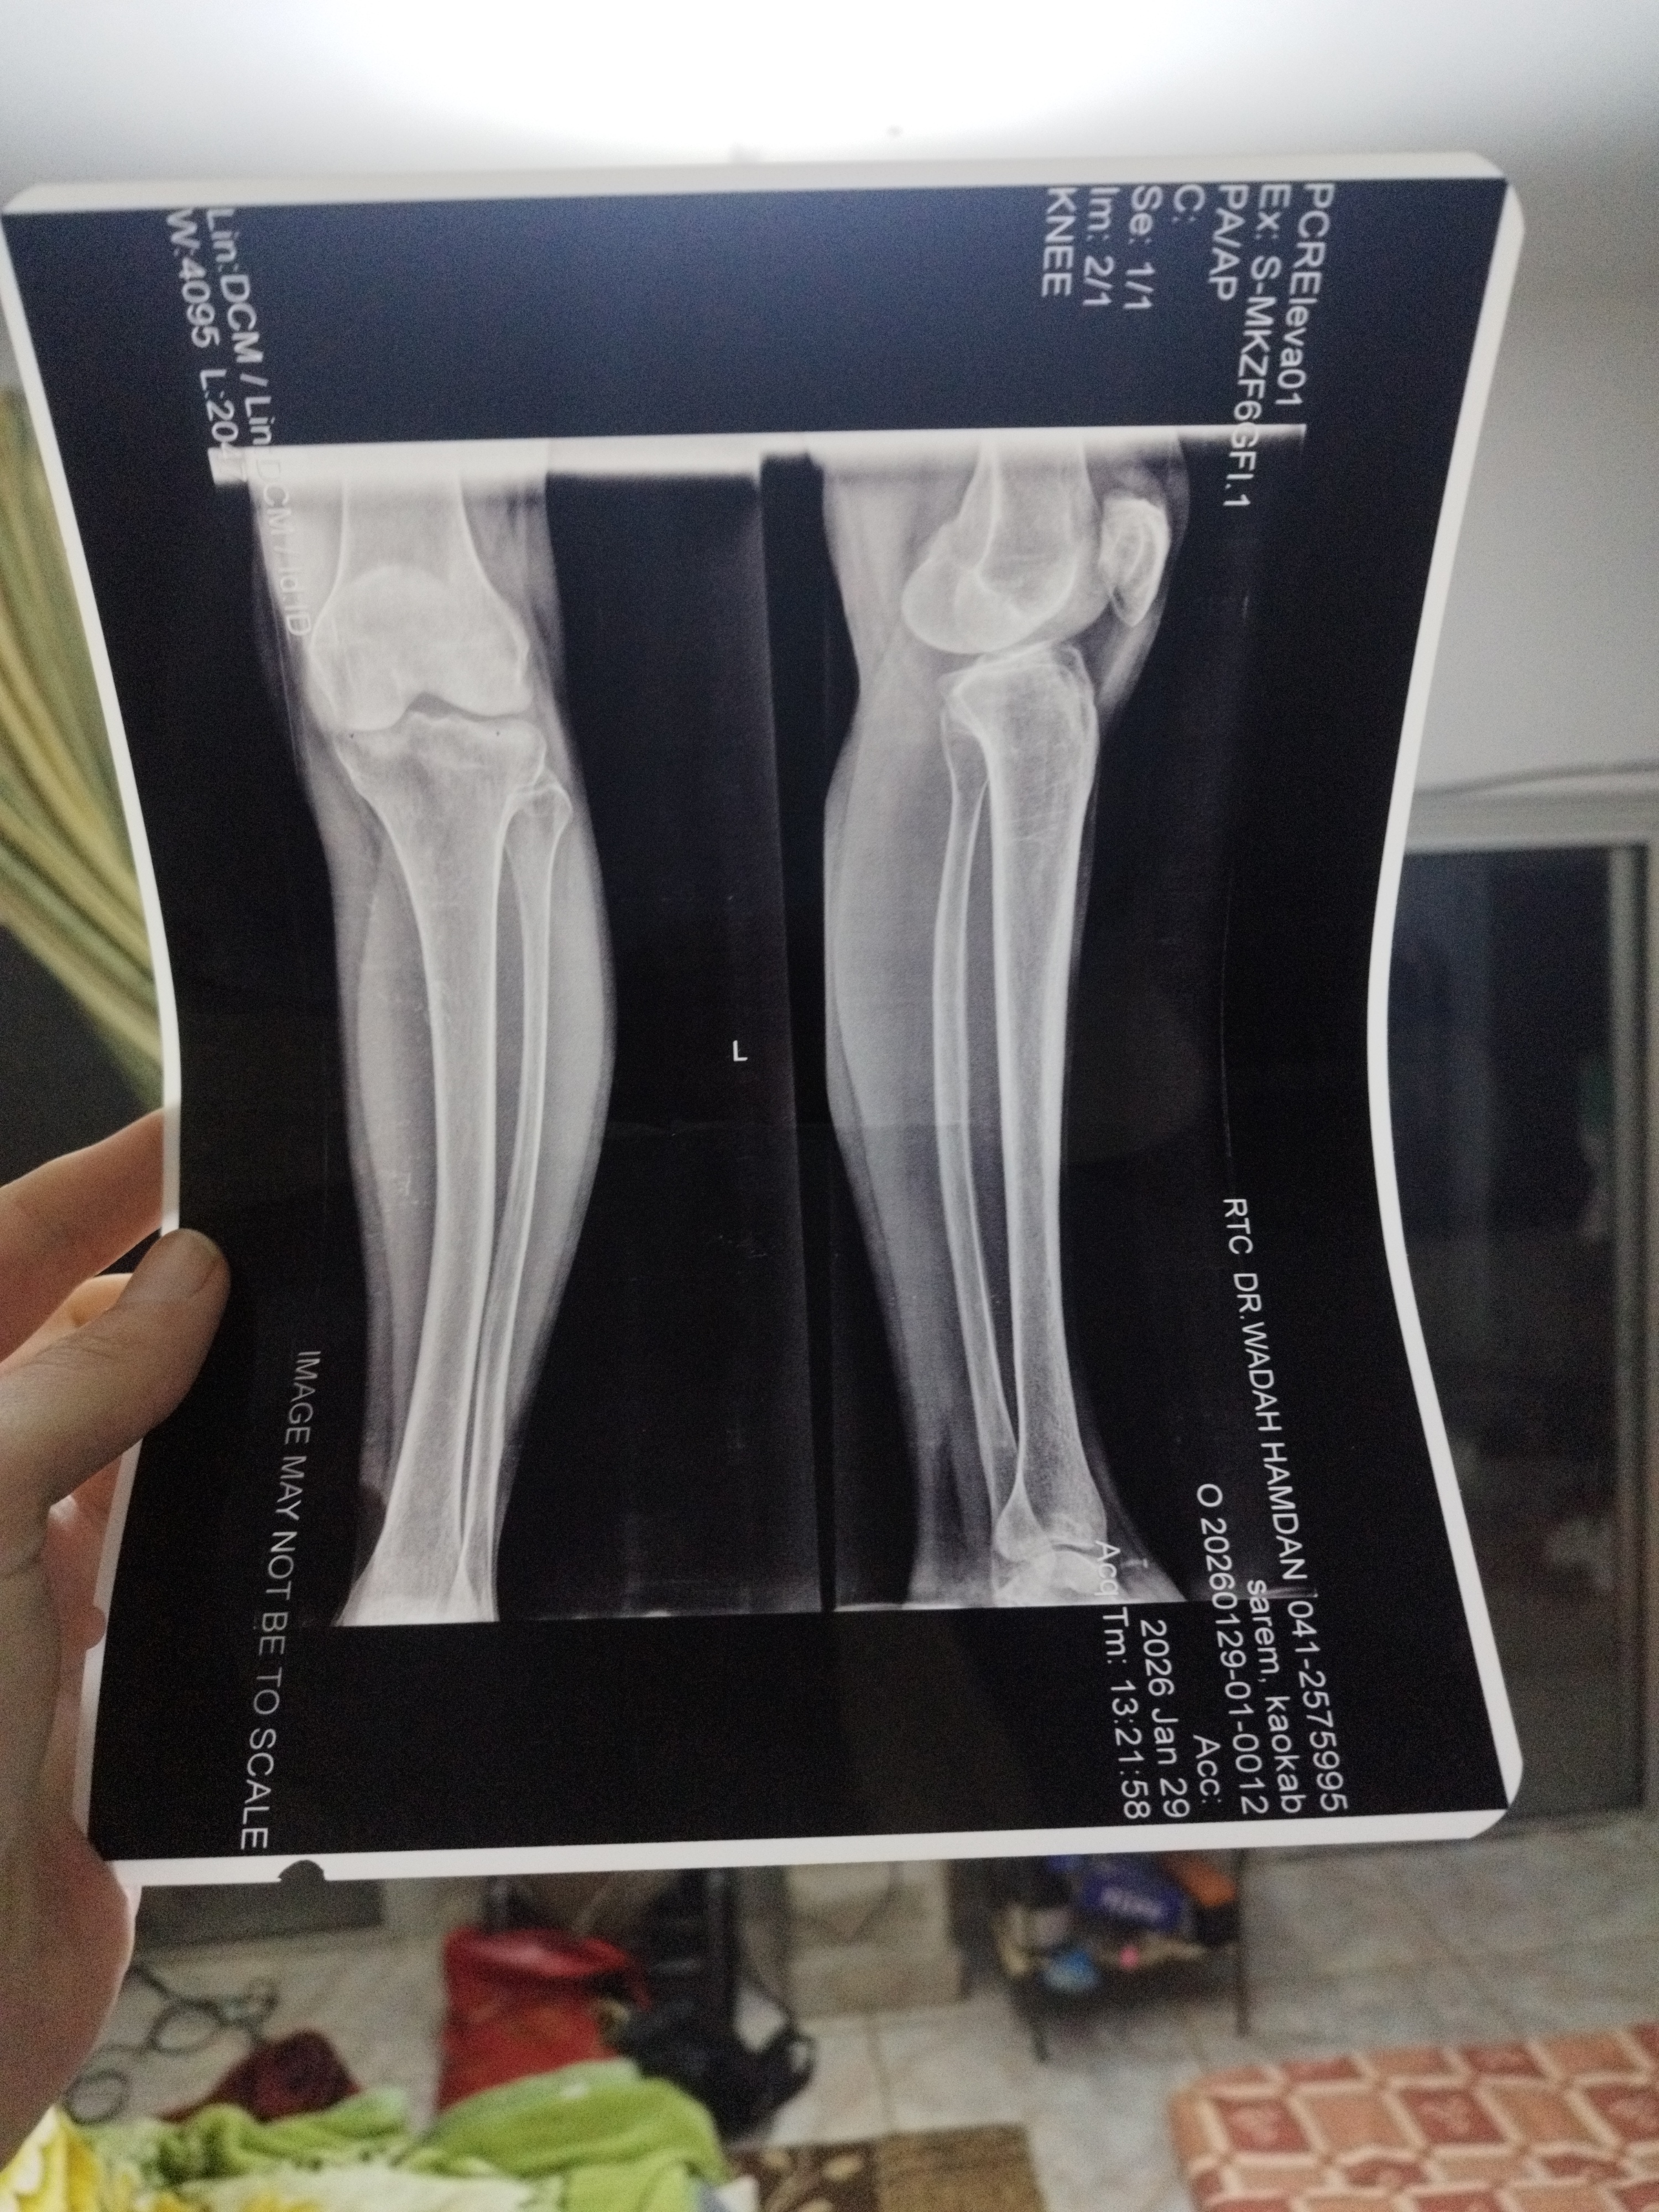

لدى والدتي وجع قوي بالرجل اليسرى فقط بدات من الربلة البطه ومن ثم القدم كامله مع الارداف ذهبنا للطبيب وبعد الفحص وصفلها مضادات التهاب وفيتامينات ومسكن قوي ولم ينفع وصورة للقدم من الركبه الى الاسفل الاطباء لم يعرفوا المشكله ابدا المسكنات لاتنفع هل يجب ان افعل شيء اخر غير صوة القدم واسفل الظهر

إجابات الأطباء على السؤال